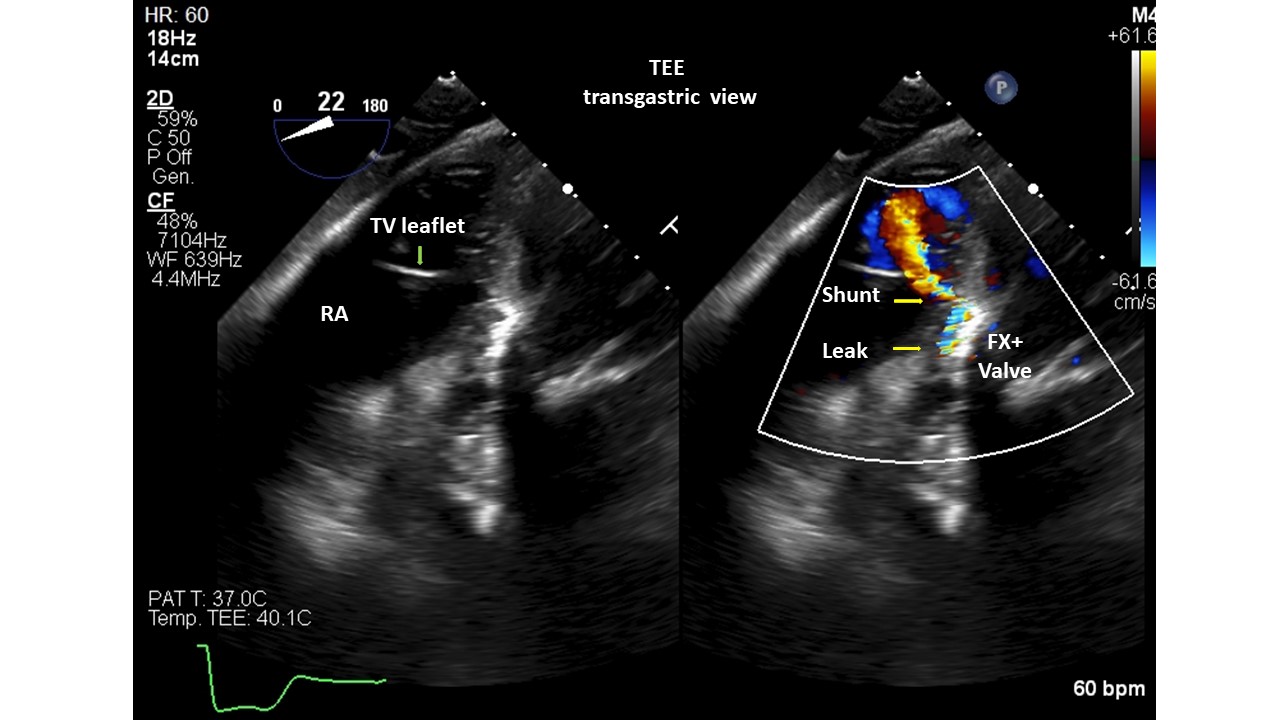

Introduction. Gerbode’s defect dates back to 1857. It generally has a congenital etiology, however very rare acquired forms have been described as complications of cardiac surgery, bacterial endocarditis, thoracic trauma, myocardial infarction or Transcatheter Aortic Valve Implant (TAVI). Diagnosing the communication between the left ventricle and the right atrium post-TAVI is not always easy, but a thorough echocardiography can lead to the correct diagnosis. We present 2 patients with Gerbode's defects post-TAVI, presumed with post-procedural transthoracic echocardiography (TTE) and validated with transesophageal (TEE) or 3D-ultrasound (3DTTE). Methods. A single-centre retrospective study of 1309 consecutive with severe aortic stenosis patients, who underwent TAVI from 2020 to 2025, was conducted with 5 types of aortic valve. All patients were evaluated with TTE before and after the procedure; only 23 patients underwent TEE. Results. Screened patients had a mean age of 82±7 years. Patients had multiple cardiac and non-cardiac comorbidities and high logistic EuroSCOREs and STS scores. Two subjects (0.15%) were found to have a Gerbode-type II septal defect. They were implanted with Medtronic Evolut FX+ valve. The calcium score of the aortic valve annulus was calculated in the 2 patients with CT (3,296 and 2,395 AU, respectively). Both prostheses were postdilated with a balloon to treat residual moderate paravalvular regurgitation. The cases were diagnosed with TEE/3DTTE to have a restrictive left to right shunt (Qp:Qs=1.4 case 1, 1.2 case 2). The patients were not symptomatic and did not require any further intervention. The mechanisms proposed for ventricular septal defect (VSD) formation: pressure exerted directly by the valve on the membranous septum, severe/asymmetric calcification of native valve, aggressive postdilatation. Conclusions. The role of TEE/3DTTE in the accurate diagnosis of these VSD suggests that it can be used as an alternative to other diagnostic tools, such as cardiac catheterization, CT and cardiac magnetic resonance imaging. Gerbode’s defect is a rare complication of TAVI and was detected more with balloon expandable valves, but can also occur with self-expanding ones. Percutaneous treatment was preferred over open cardiac surgery. Some, but not all, patients survived TAVI and VSD, and had a good prognosis for both patient groups with or without VSD closure. Careful follow-up with a dedicated team is essential in these patients.